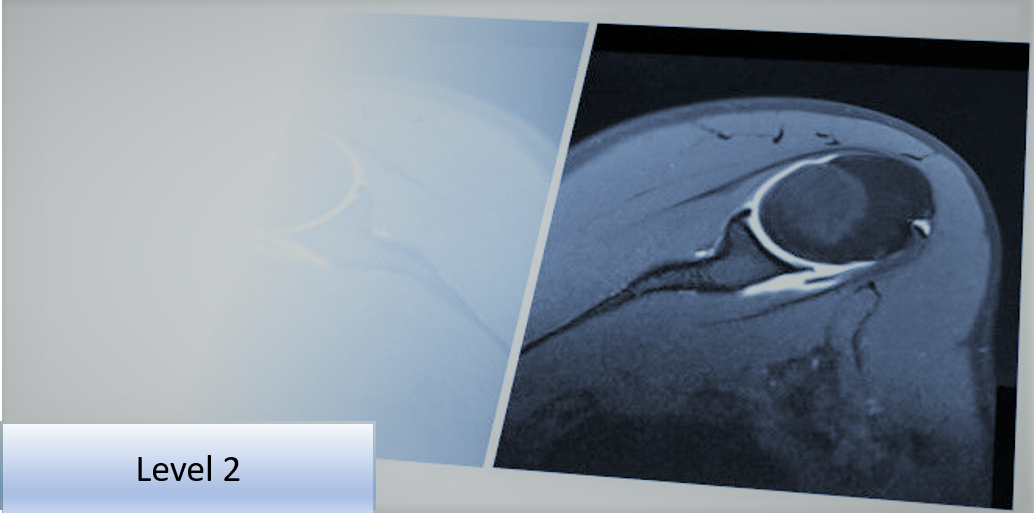

Level 2 Further Skills: Musculoskeletal Imaging Referral and Interpretation - Upper Limb

This Level 2 course will provide the delegate with further skills and understanding to improve diagnostic imaging use and ensure it is clinically appropriate, thereby supporting clinical examination of the upper limb.